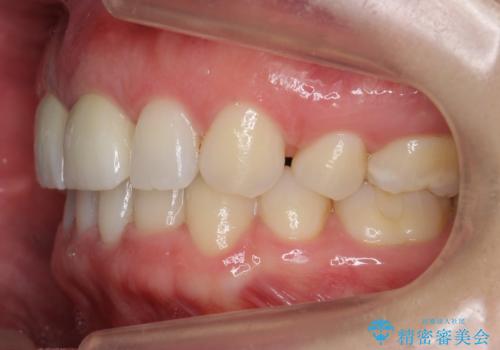

- 前歯が2本出っ歯だったのを、他院でセラミックにしたが、口元が突出しているのが治らないとのことでした。

セラミックにする際に神経をとり、無理やり歯の頭の部分のみ内側に引っ込めてありました。

出っ歯が厳しい方は、歯の頭の部分だけ被せて角度を変えても、根元は変わらないため、口元は下がりません。